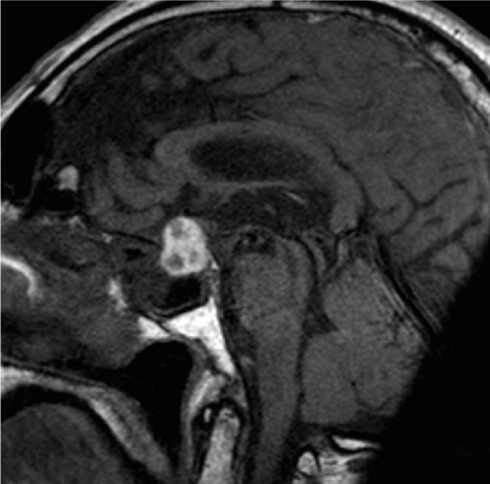

A 77 year-old man with no significant medical history presented with sudden onset febrile headache and blurred vision. Clinical presentation was mimicking bacterial meningitis with nuchal rigidity, fever and hypotension. Clinical exam revealed variable left upperlid ptosis and diplopia. A lumbar puncture was immediatly performed. Cerebral spinal fluid analys is revealed an increased leukocyte count (73/μL), with neutrophilic granulocytes predominating (88%), increased total protein content (1.7 g/L), and glucose level 3.5 mmol/L. The gram staindid not demonstrate any microorganisms. CRP was elevated (184mg/L). Antibiotics were immediatly started (Amoxicillin and Ceftriaxon). The headaches, the diplopia and the general condition did not improve after 24 hours of antibiotics, an MRI of the brain was performed and showed a pituitary mass lesion compatible with pituitary macro-adenoma with intrinsic hemorrhage. High-dosage steroid therapy (Dexamethasone 10mg/6hours) was started on the hypothesis of pituitary apoplexy and his condition rapidly improved. The diagnosis was confimed biologically as pituitary functions were dramatically decreased (IGF-1: 63 ng/mL, GH: undetectable, TSH 0.02 µU/mL, free T4 16.9pmol/L, unadapted level of adrenocorticotrophic hormone (ACTH) 20pg/mL (2-50 pg/mL), basal cortisol 80 µmol/L (275-685 µmol/L), Follicle-Stimulating Hormone (FSH) 1.9 mU/mL (20-100 mU/mL), Luteinizing Hormone (LH) 0.3mU/mL (> 20 mU/mL), testosterone 0.11ng/mL (2.7-7.8 ng/ml) and prolactin 1 ng/L (3-25 ng/L). There was no initial sign of diabetes insipidus.

Surgical treatment was not needed as his neurological condition completeley recovered after 3 months of steroids. A second MRI showed dramatic decrease in size of the adenoma a month later. All the pituitary axis recovered after 3 months of steroid treatment except the corticotrop function. He is still on hydrocortisone 6 months later and is doing perfectly well